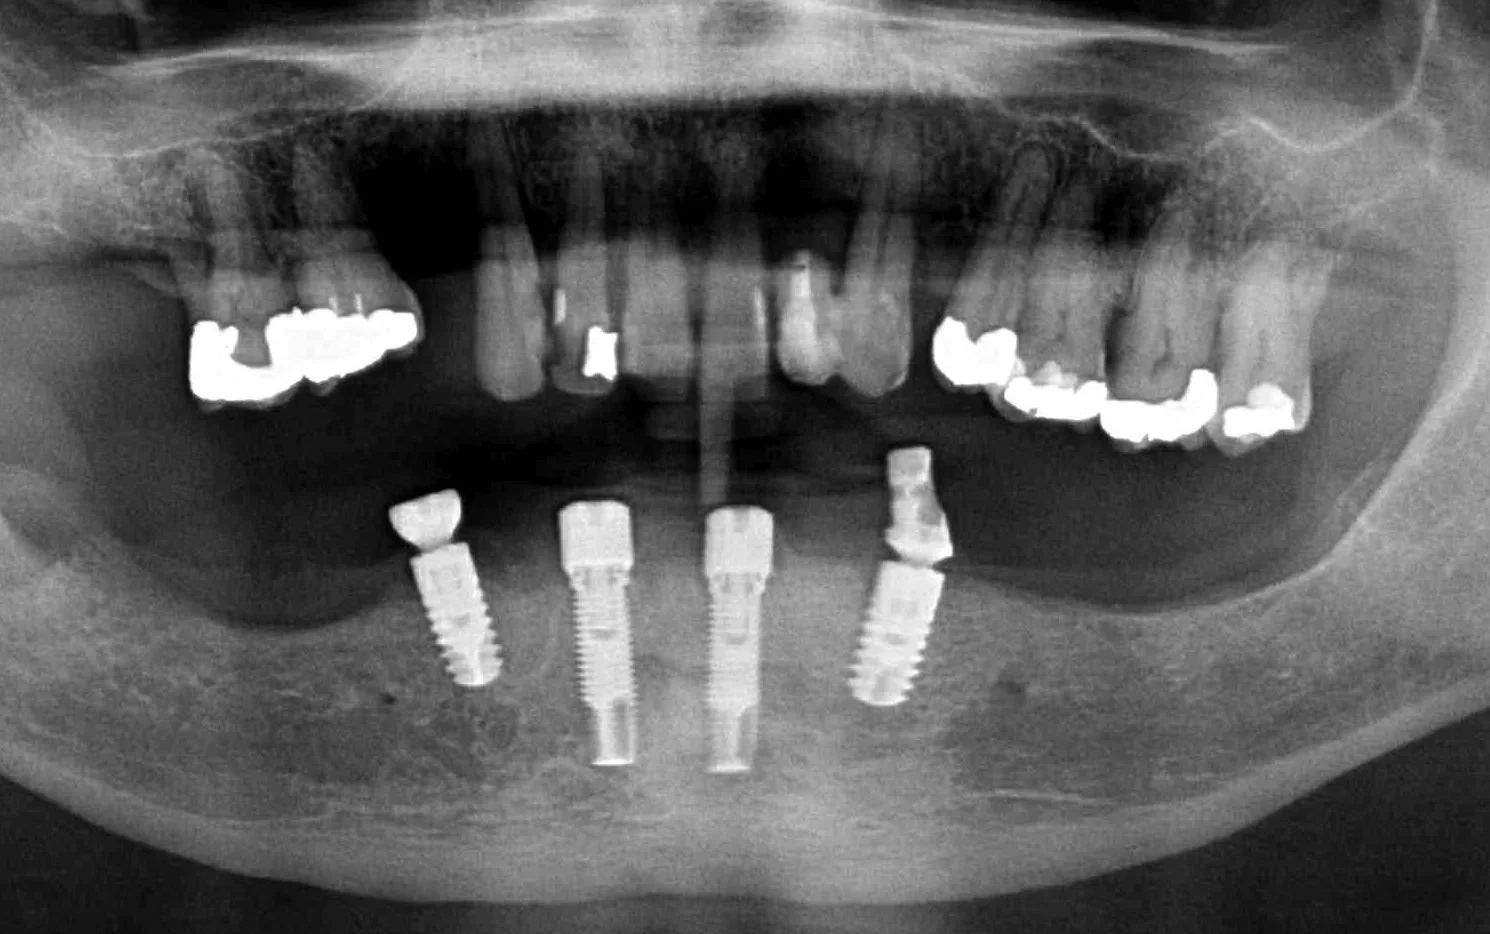

An OPG radiograph illustrating a variety of dental concerns and the presence of 2 implants in the lower jaw in the first premolar regions, namely, 34 and 44.

-

An OPG radiograph after the 6 extractions and Dr. Darveniza in 2014 surgically placed 2 Branemark implant fixtures between the existing 2 Ankylosis implant fixtures along with some artificial powdered RTR bone. Bone grafting adjacent to these Ankylosis implants was required following the extraction of the lower canines which had bone loss adjacent the 34 and 44 implant fixtures.